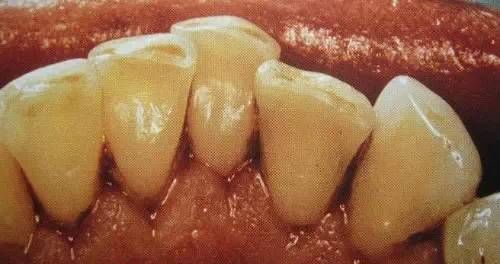

一个高职学校的学生,口腔内严重的牙结石,可能小时候没有刷过牙

洗牙(洁治)后效果很明显